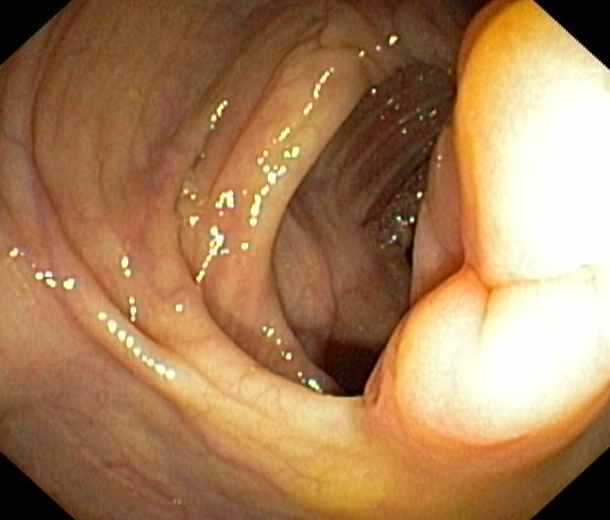

Ileocaecal valve